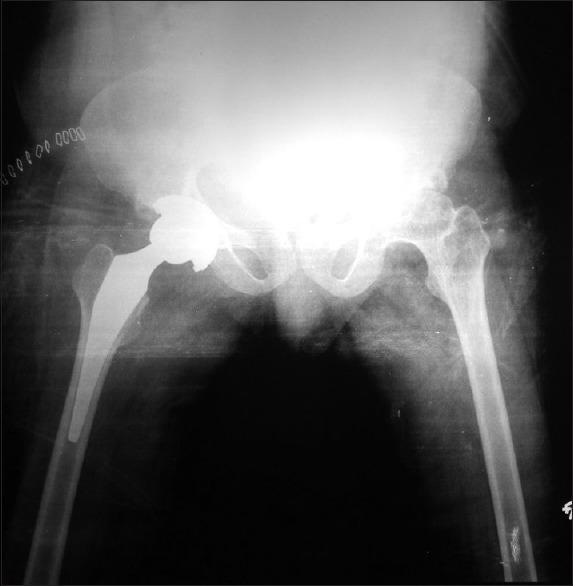

Legg-Calve-Perthes disease: A must know entity for anaesthesiologists.

https://cdn.ncbi.nlm.nih.gov/pmc/blobs/c391/4782432/4d93192d398a/IJA-60-68-g001.jpg